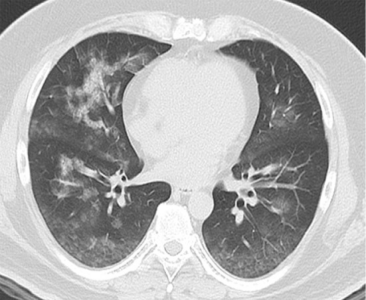

白细胞计数9.830/Mm³(轻度升高);初始高敏肌钙蛋白T(Hs-TnT)0.013ng/ml(正常),4小时后升至0.044ng/ml(未达第99百分位值0.52ng/Ml);初始N末端脑利钠肽前体(Nt-ProBNP)49pg/ml(正常),次日升至 137pg/ml。心电图(ECG):窦性心动过速,无明显St-T改变(图1)。超声心动图(入院时):左心室无扩大,室间隔厚度8mm,左心室后壁厚度9mm,舒张末期直径45mm,收缩末期直径30mm,左心室射血分数(EF)62%,室壁运动正常。胸片及胸部CT:均提示肺淤血(图2、图3)。心肌闪烁显像(入院第5天):201 - 铊显像示左心室中度灌注缺损,123I-Bmipp 显像示左心室前壁、下壁摄取严重减少,提示灌注-代谢不匹配(图4)。超声心动图(入院第5天):EF 56%,E/e' 12.3,中隔 e' 5.2cm/s,三尖瓣反流速度 2.9m/s,左心房容积指数 25ml/m²。

(图3)